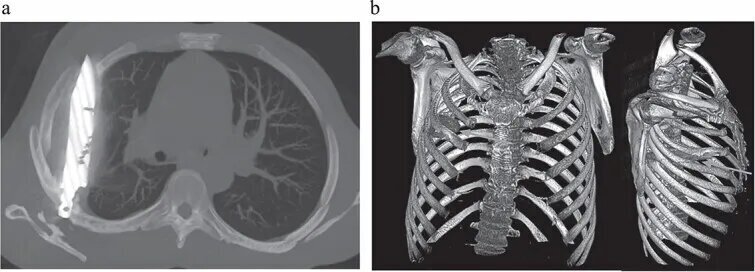

تصویربرداری با اشعه ایکس و سیتیاسکن نشان داد تیغهایچ بزرگ از چاقو از پشت قفسه سینه وارد شده، بین دندههای پنجم و ششم گیر کرده و نوک آن تا جلوی قفسه سینه بین دندههای سوم و چهارم امتداد یافته است. شکستگیهای ترمیمشده در استخوان کتف و چند دنده نیز مشاهده شد. همچنین اطراف تیغه، بافت مرده و چرک تجمع یافته بود.